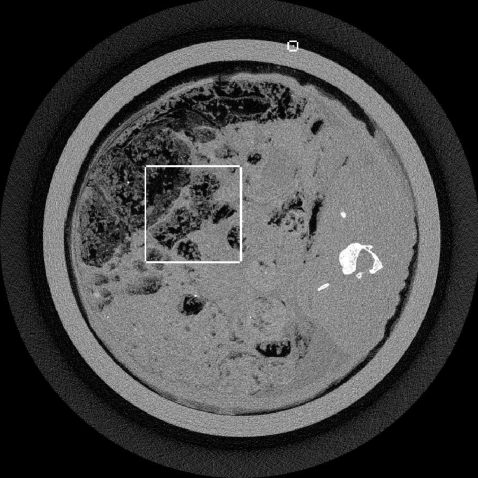

Refer to caption

Figure 1: FBP slice image of a rabbit scanned by a low-dose XCounter CT system. The raw FBP image was smoothed by a Gaussian filter, reducing the image TV by a factor of 8. The indicated rectangles show the ROIs which are used for the algorithm comparisons. In particular, the small one surrounds the wire object used to obtain a sense of resolution. The display window is [0,0.04] mm-1.

The up-sampling and frequency constrained ASD-POCS algorithms are demonstrated with an XCounter CT scan of a rabbit with a thin wire taped to the outside of the sample holder. The data are low-intensity and contain 1878 projections with a 2266x64 bin detector at a resolution of 0.1 mm. The thin wire provides a good resolution test for the image reconstruction algorithm. For the present purpose, we take the middle row on the detector from this data set and focus on 2D fan-beam CT reconstruction with 1878 projections on a 2266-bin linear detector array.

An FBP image of this data set is shown in Fig. 1, where some regularization is performed by Gaussian smoothing with a window 2 pixels wide. The rectangles indicate the regions where comparisons of the different algorithms are shown. Comparisons for each algorithm will be made at a level of image regularization where each image’s TV-norm is an eighth of that of the unregularized FBP image. The images are shown just to give a sense about the behavior of the algorithms; more rigorous evaluation with different levels of regularization will be performed in future work.